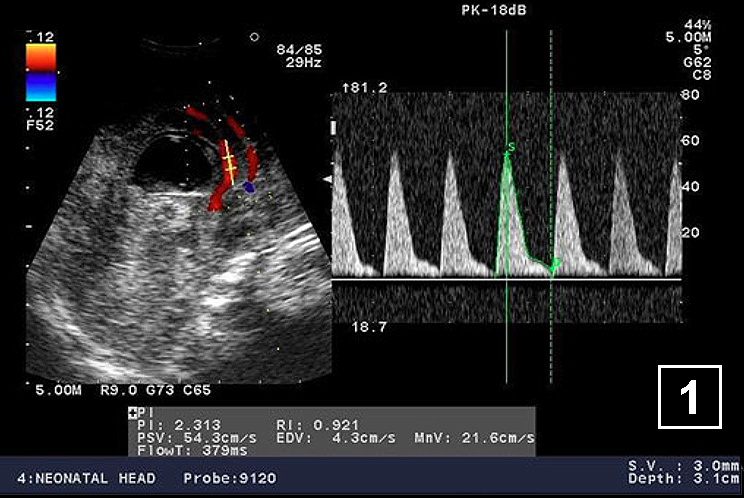

Neonatology Hydrocephalus Doppler 1 Image